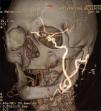

Tras este hallazgo, se realiza una consulta a nuestro servicio, que solicita un estudio hemodinámico preoperatorio completo para determinar la estrategia terapéutica. Dúplex: oclusión extensa de la carótida primitiva, flujo invertido en carótida externa (ACE) y, finalmente, ACI permeable con ondas Doppler de flujo normal (Fig. 2). Dúplex transcraneal: arteria cerebral media izquierda (ACM) con ondas de flujo normal y velocidades pico sistólicas de 110cm/s. No hay inversión del flujo intracraneal de cerebral anterior ni del resto de arterias del polígono de Willis.

Se interviene al paciente con anestesia general. Intraoperatoriamente se observa pseudoaneurisma por rotura completa de la sutura de la endarterectomía previa con moderada reacción inflamatoria perianeurismática. Así mismo, hay presencia de pulso en el origen de la ACI, que desaparece tras el pinzamiento de la ACE proximal. Se practica resección del pseudoaneurisma y anastomosis en terminoterminal de ACE sobre ACI tras la ligadura de la arteria tiroidea superior. En el postoperatorio no hay incidentes de interés. No se observan eventos neurológicos ni lesión de pares craneales. Se realiza un cultivo de pared positivo a Staphylococcus aureus. Se inicia tratamiento con cloxacilina durante seis semanas y el paciente es dado de alta con antiagregación simple. Tras un mes de seguimiento se practica angio-TC de 64 coronas que confirma la permeabilidad de la técnica y la ausencia de colecciones o signos de sobreinfección (Fig. 3). Se hizo un control a los seis meses mediante dúplex sin anomalías reseñables.